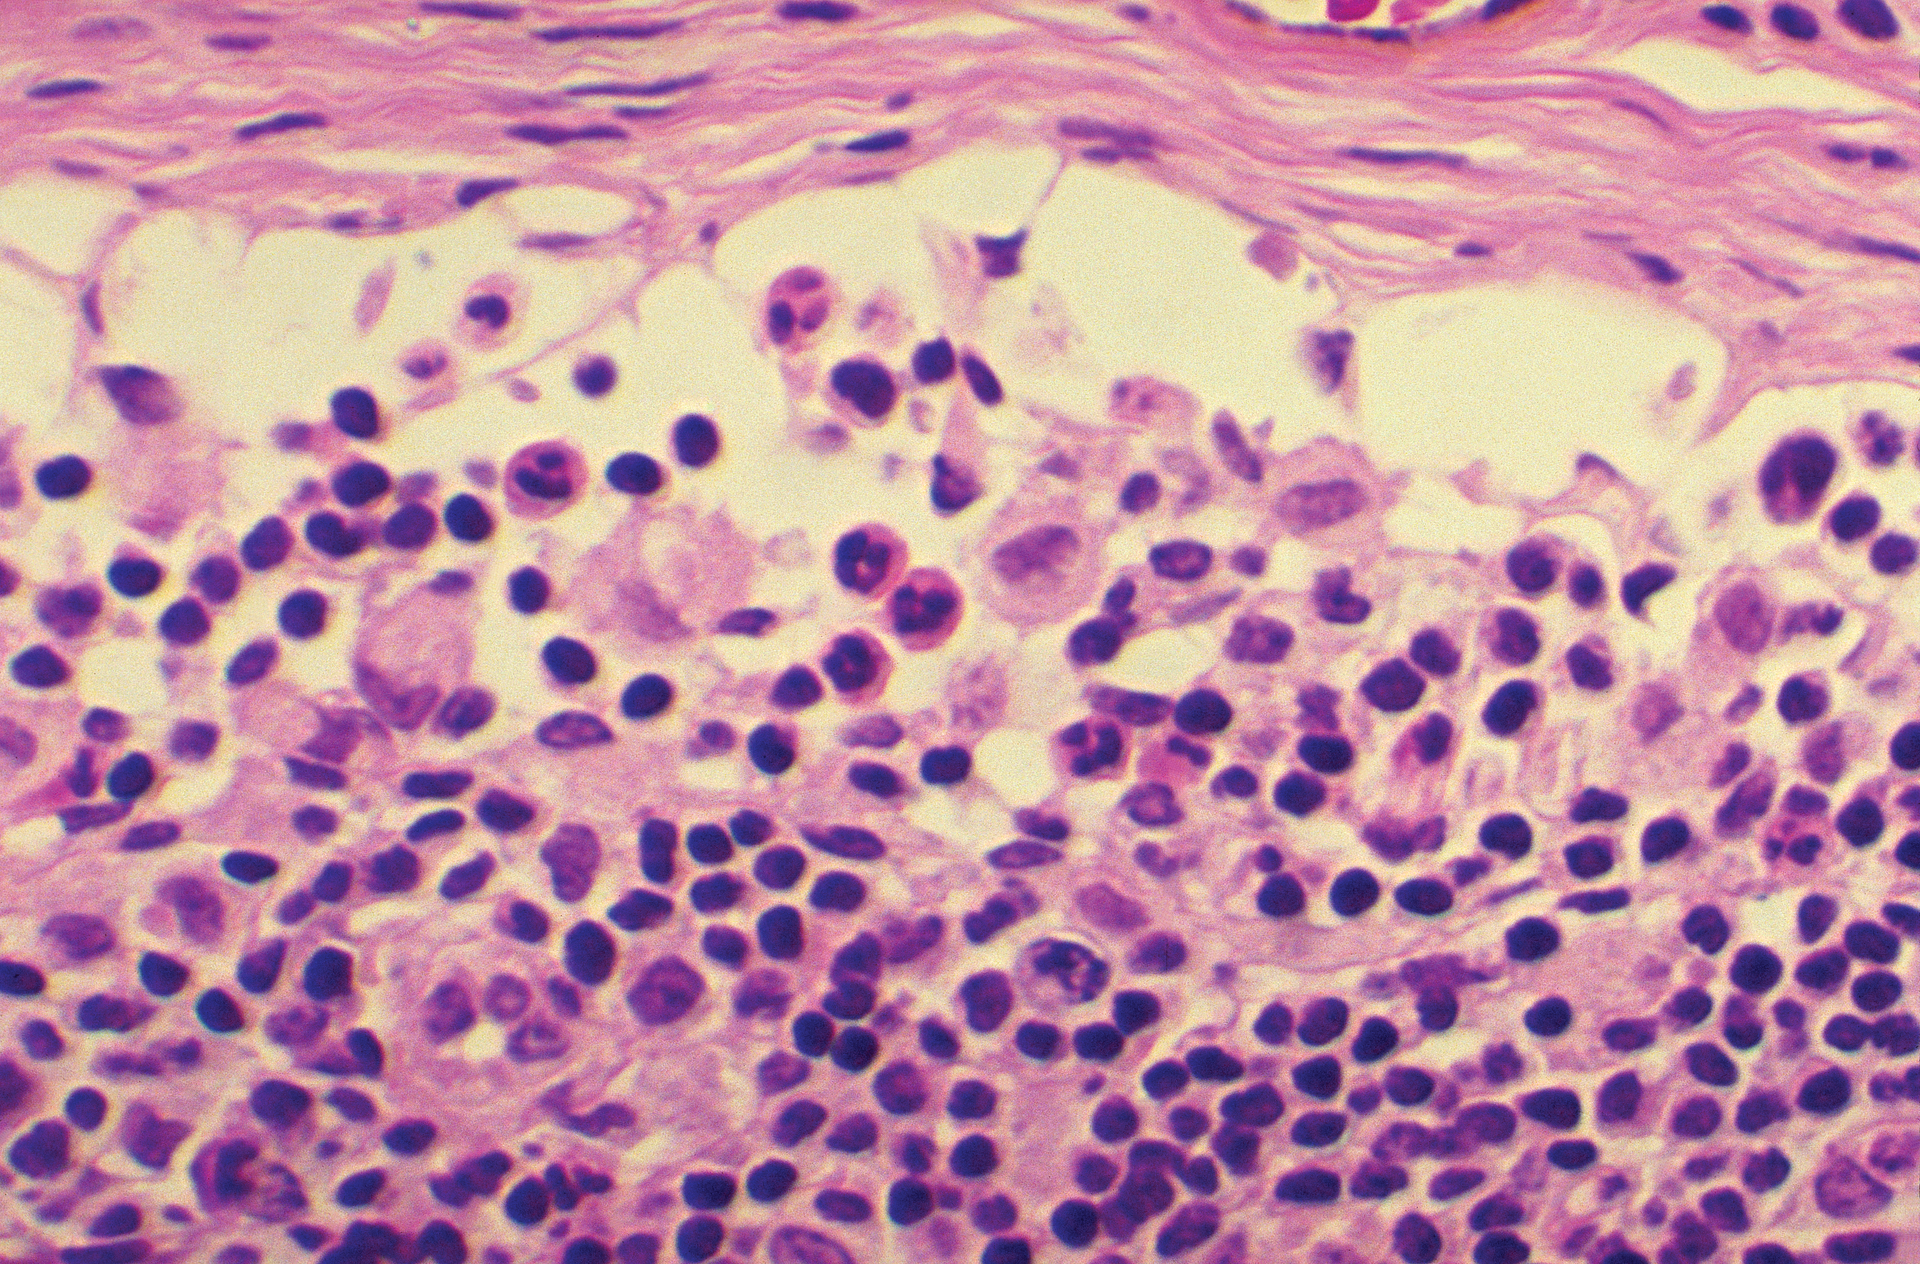

Another important but complex area of research is SARS-CoV-2 co-infection, where an individual may be infected with the virus and one or more additional pathogens concomitantly. SARS-CoV-2 infection leads to both innate and adaptive immune responses, which, in some cases of severe disease, can become dysfunctional and cause significant lung and systemic pathology. 2 This lung damage and dysregulated immune response in severe COVID-19 pneumonia puts these patients at an increased risk of secondary infection. In addition, individuals with pre-existing conditions could be more susceptible to severe COVID-19 disease if infected.

Although the reported incidence of bacterial, fungal, and viral co-infections in hospitalized COVID-19 patients is relatively low 3 when present, they may cause severe diseases with poorer outcomes. For example, many studies have reported a higher incidence of secondary infections in patients admitted to the ICU,4,5 and those diagnosed with secondary infections had lower discharge rates and higher mortality rates than those without secondary infection.6 Researchers are still looking to determine whether this outcome is a function of longer ICU stays, concomitantly administered medications (e.g., antibiotics, immunomodulators), the immunocompromising effects of severe COVID-19 itself, or other factors.7